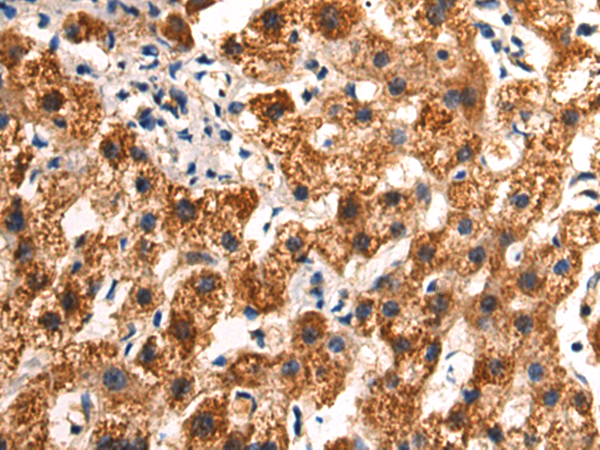

分类: 科研抗体货号: P07128别名: GAF; FGF-9; SYNS3; HBFG-9; HBGF-9应用: WB,IHC反应种属: Human, Mouse, Rat